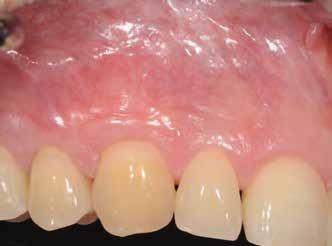

uni.fit titánalapra (bredent medical). Az implantátum körül a bukkális lágyszövet megfelelő vastagságot és kedvező ínykontúrt mutatott (12. a–b. ábra). Az egyedi ínyformázó eltávolítása után egészséges implantátum körüli lágyrészgallér

értünk el (19. ábra). Az okkluzális nyílást tefloncsíkkal és kompozittal zártuk (20. ábra). Mindezek után, posztoperatív kontroll röntgenfelvétel készült, amely a pótlás megfelelő illeszkedését mutatta (21. ábra). A hat hónapos utánkövetés során jól megfigyelhető a teltebb lágyszöveti profil és a megtartott kresztális csontszint (22–24. ábra)

volt megfigyelhető (13–14. ábra), ezen kívül közvetlenül a műtét előtt intraorális vizsgálatot végeztünk a lágyszöveti profil megállapítása érdekében. Ezt követte a scanbody behelyezése, így digitális lenyomat készült az implantátum pozíciójáról (15. ábra). Ugyanezzel a technikával rögzítettük az antagonista fogívet és a harapást is. Az így kapott STL-fájlokat digitálisan továbbítottuk a fogtechnikai laboratóriumba. A titánalapra PMMA ideiglenes koronát készítettünk a proximális és marginális illeszkedés ellenőrzése érdekében, valamint a megfelelő harapás elérése céljából (16–17. ábra) Miután az összes igazítás elkészült, ismételt vizsgálatot végeztünk. A végleges hibrid csavarrögzítésű, teljes kontúrú cirkóniumkoronát titánalapon erősen polírozott szubgingivális résszel készítettük el, és 25 Ncm nyomatékra húztuk (18. ábra). Kiváló árnyalategyezést és klinikai eredményt